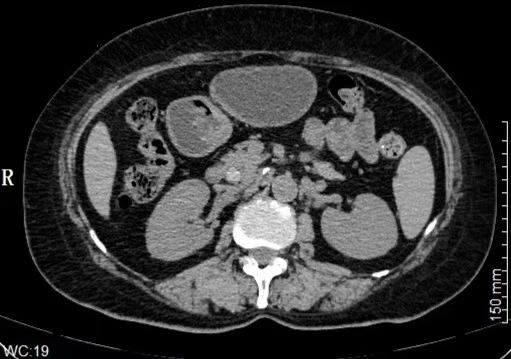

赵女士现年59岁,右中上腹间断性疼痛持续10年。为祛除病痛,于3月3日来吉林省肝胆病医院肝胆外科就诊。主治医师钱峰通过查体发现,患者右上腹压痛明显,结合腹部彩超、CT及MRCP检查,确诊其存在胆总管结石伴胆管炎,并且还患有胆囊结石伴慢性胆囊炎急性发作。

△该图片非案例提及

△该图片非案例提及